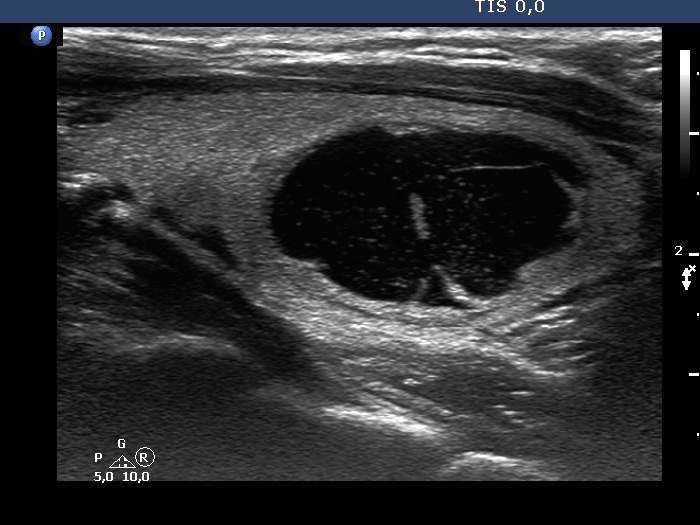

Second examination 4 years later (second and third rows of images):

Clinical presentation: The patient had no complaints.

Palpation: unchanged.

Result of blood test: TSH 1.52 mIU/L.

Ultrasonography. The cystic nodule had refilled. The presentation remained the same.Seven mL brown fluid was aspirated. Cytology: benign, cystic lesion.

Suggestion: ultrasound in two years.